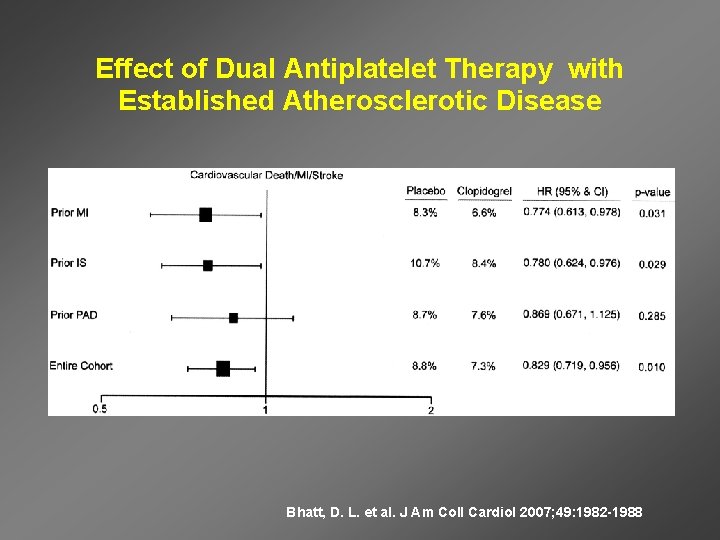

Effect of Dual Antiplatelet Therapy with Established Atherosclerotic Disease Bhatt, D. L. et al. J Am Coll Cardiol 2007; 49: 1982 -1988